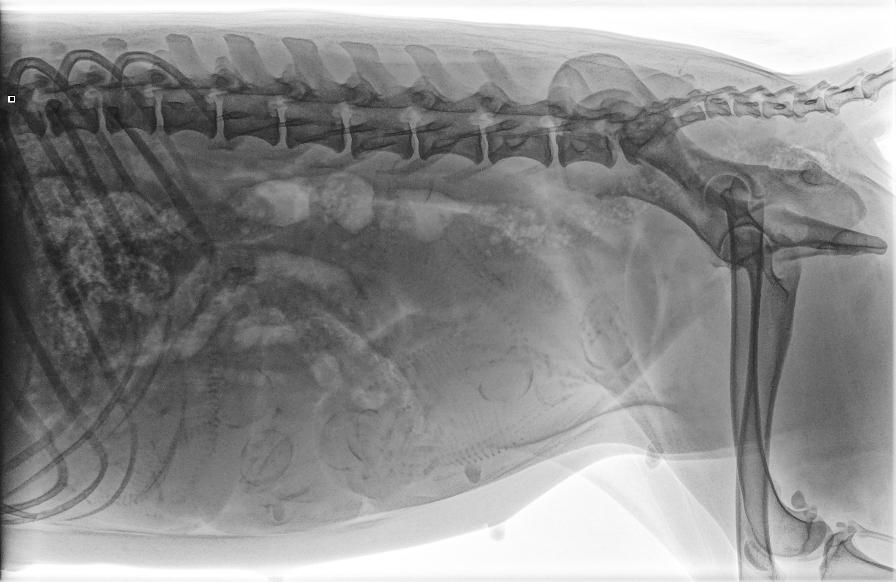

Wir waren im röntgen und haben ganz viele Breebobs gesehen...nun freuen wir uns ganz arg auf die kleinen Babys, welche gegenEnde April auf die Welt kommen werden...